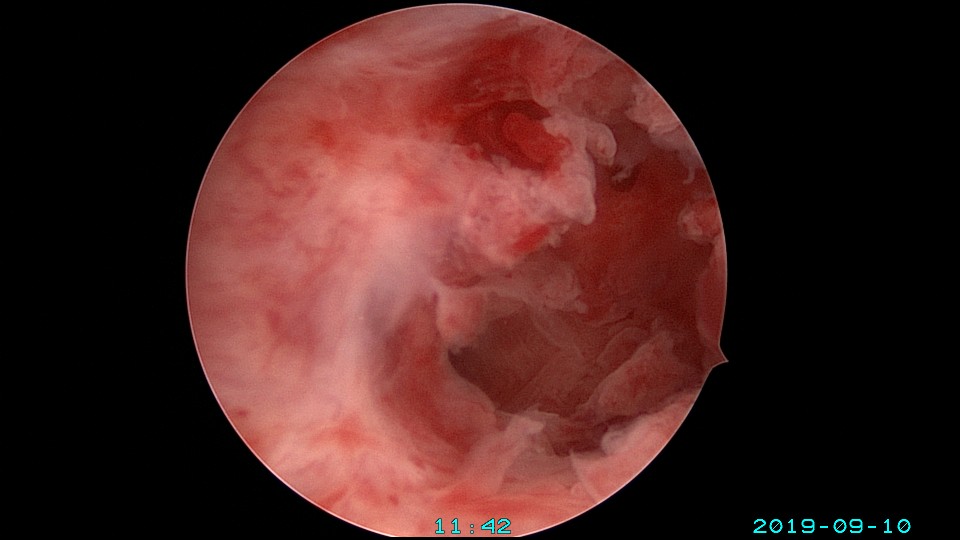

患者26岁,G1P0 ,2019年9月门诊宫腔镜检查发现宫腔重度粘连,2019年10月住院宫腔镜分粘,恢复宫腔形态,显露双侧输卵管开口。2019年11月宫腔镜二探取球囊,宫腔形态正常,双侧输卵管开口可见。2021年3月发现自然妊娠,后因先兆流产、胎心弱在当地医院险些清宫终止妊娠,病人电话咨询我,嘱病人千万不要急着清宫,立即到我院复查,心管搏动良好,住院保胎成功,2021年11月,39周孕剖宫产分娩。2023年7月,再次自然妊娠,39+3周孕剖宫产分娩。现31岁,G3P2。